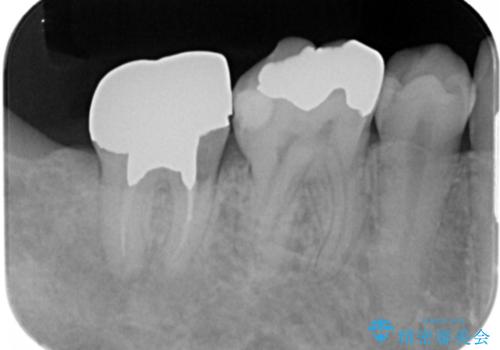

右下の被せ物を外し虫歯を除去したところ虫歯が深く保存が難しい状態だったので抜歯を行いました。

手前の銀の詰め物のところは除去して拡大鏡下で虫歯を取り除き、ジルコニアクラウンで治療を行いました。